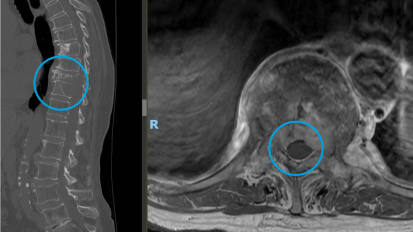

Performing a Minimally Invasive Approach for Spinal Tumor Resection

Johns Hopkins neurosurgeons eschew open surgery to help a patient with metastatic breast cancer quickly return to her active lifestyle.